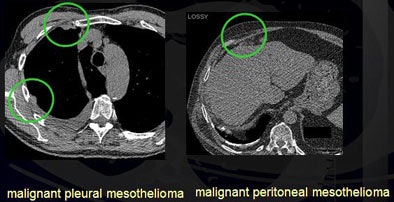

In addition, the researchers found two malignant pleural mesotheliomas and one malignant peritoneal mesothelioma, for an overall malignancy rate of 1.4% to 1.9%.

| Detected malignancies included malignant pleural mesothelioma and malignant peritoneal mesothelioma. |